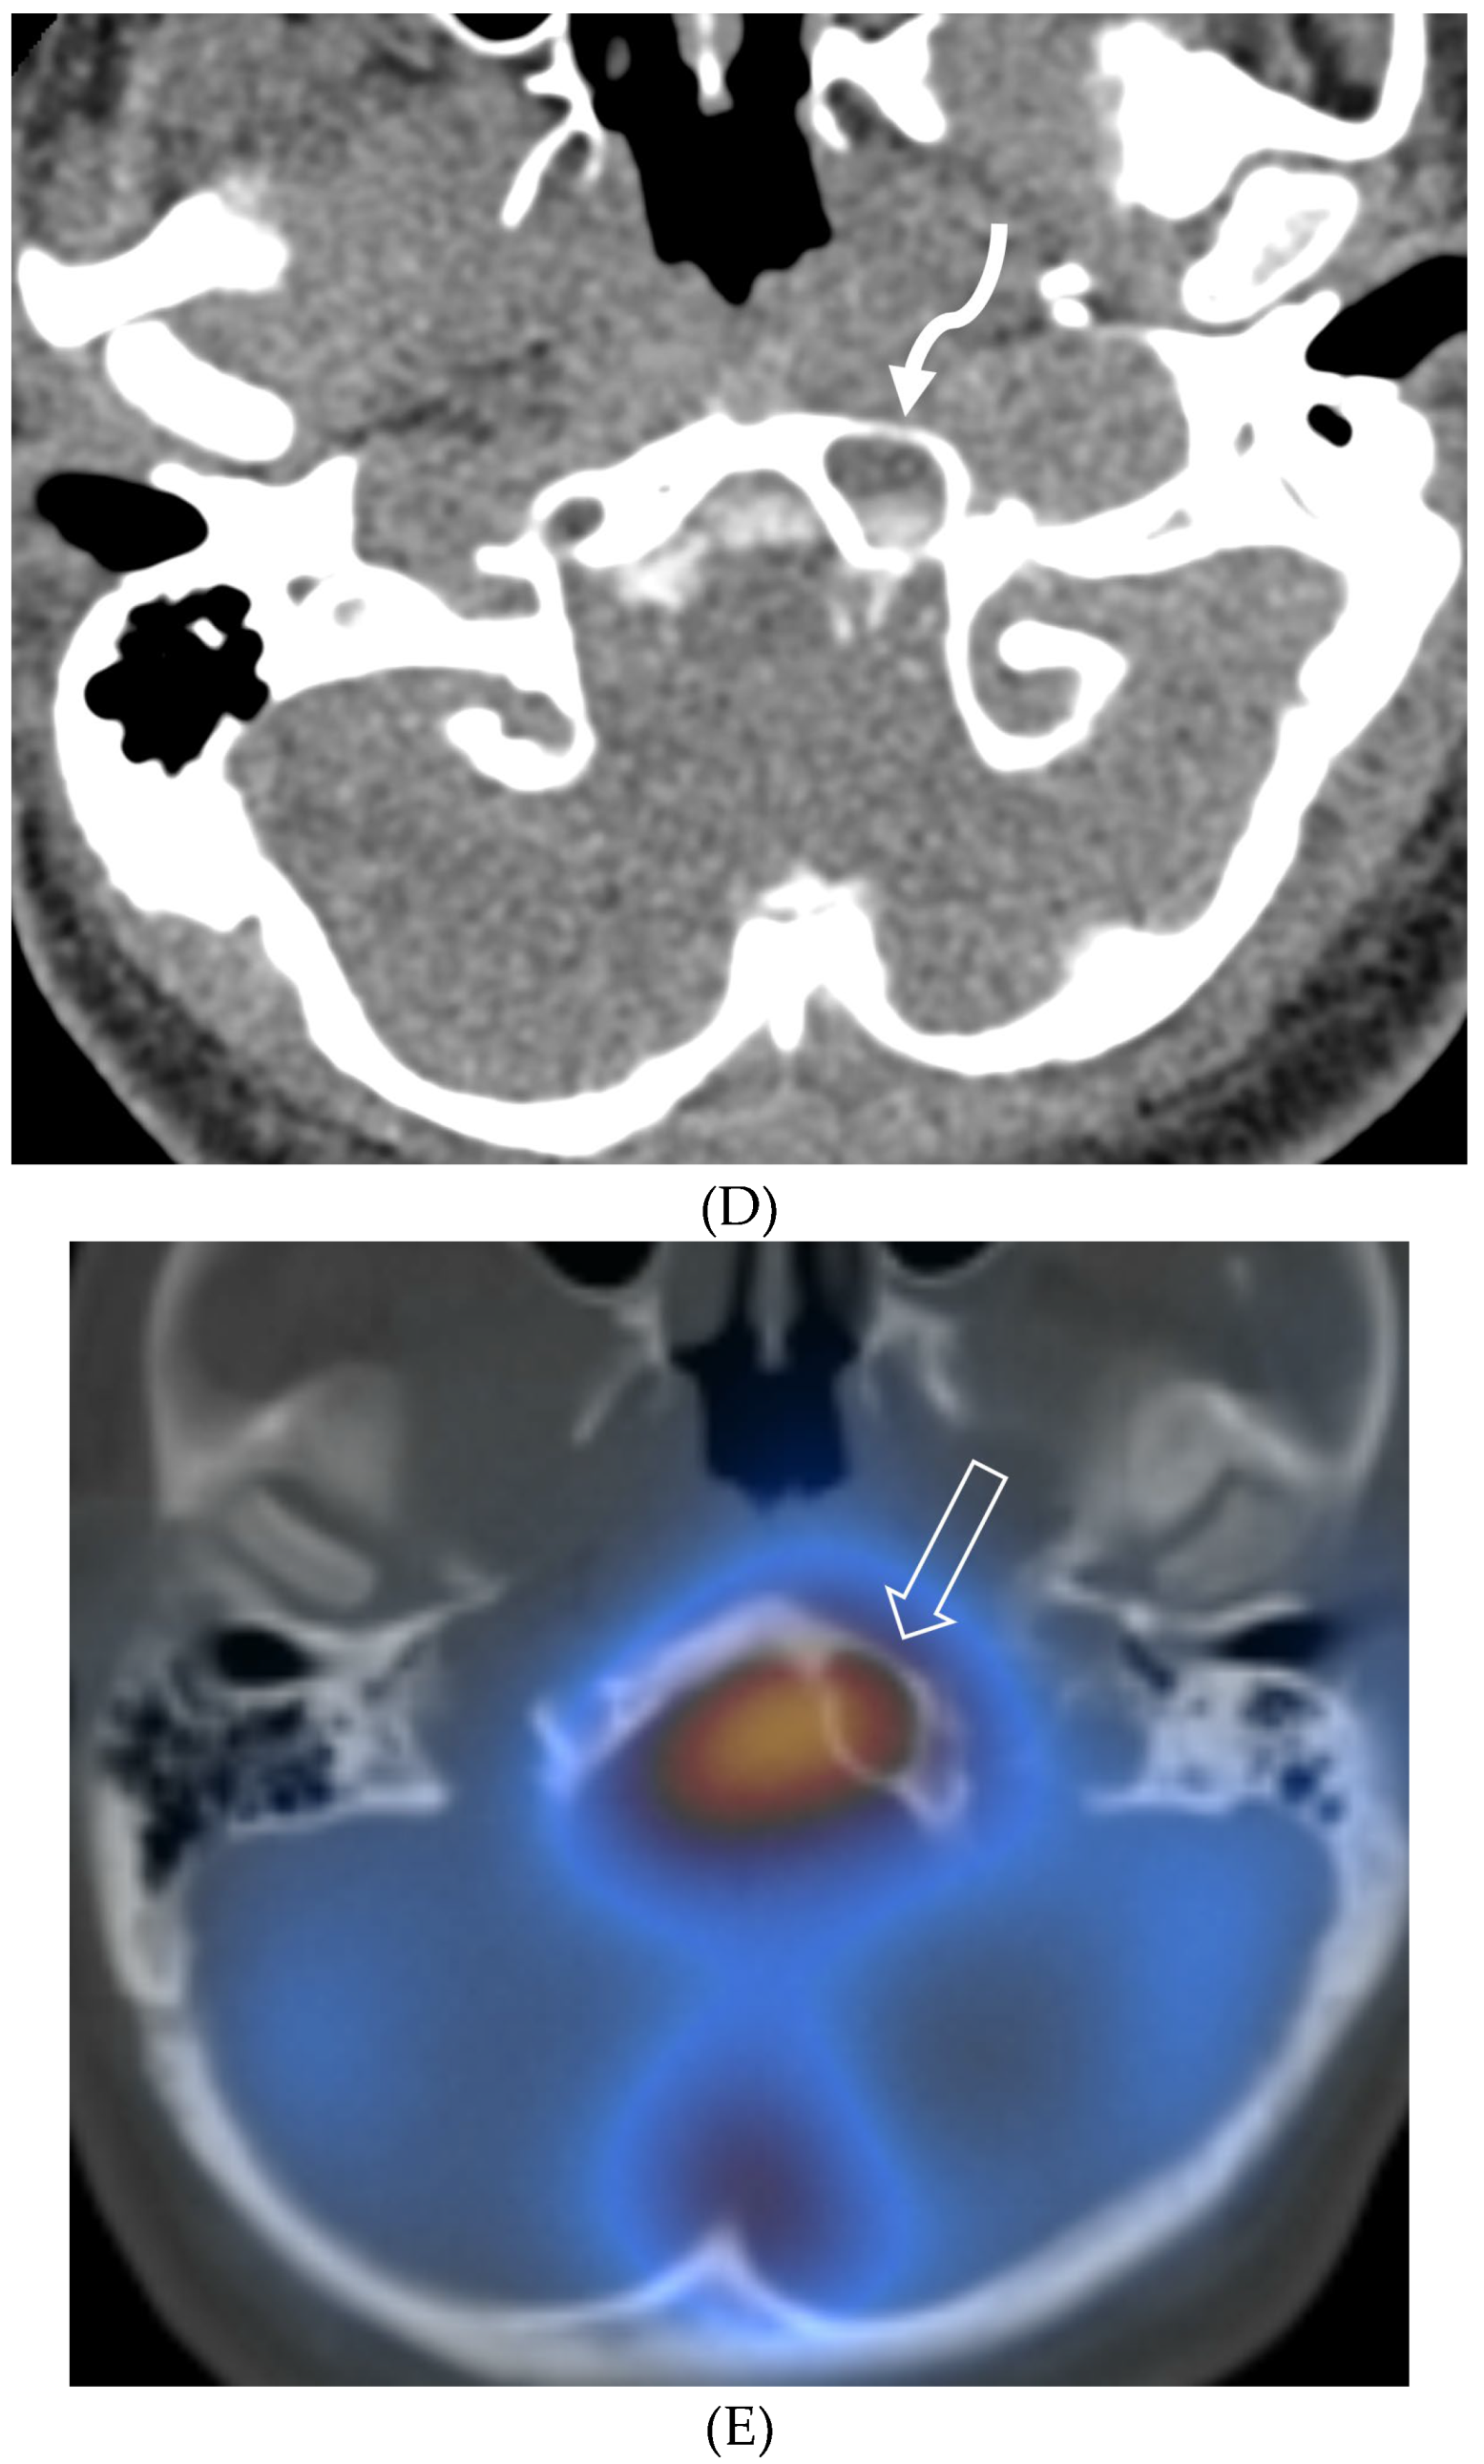

- Tajmalzai A, Shirzai A, Najah DM. Early manifestation of Moyamoya syndrome in a 2-year-old child with Down syndrome. Radiol Case Rep. 2021 May 1;16(7):1740-1744. PMID: 34007395; PMCID: PMC8111440. [CrossRef]

- Horie N, Morikawa M, Nozaki A, Hayashi K, Suyama K, Nagata I. "Brush Sign" on susceptibility-weighted MR imaging indicates the severity of moyamoya disease. AJNR Am J Neuroradiol. 2011 Oct;32(9):1697-702. Epub 2011 Jul 28. PMID: 21799039; PMCID: PMC7965393. [CrossRef]

- Ohta T, Tanaka H, Kuroiwa T. Diffuse leptomeningeal enhancement, "ivy sign," in magnetic resonance images of moyamoya disease in childhood: case report. Neurosurgery. 1995 Nov;37(5):1009-12. PMID: 8559324. [CrossRef]

- Maeda M, Tsuchida C. "Ivy sign" on fluid-attenuated inversion-recovery images in childhood moyamoya disease. AJNR Am J Neuroradiol. 1999 Nov-Dec;20(10):1836-8. PMID: 10588105; PMCID: PMC7657767.